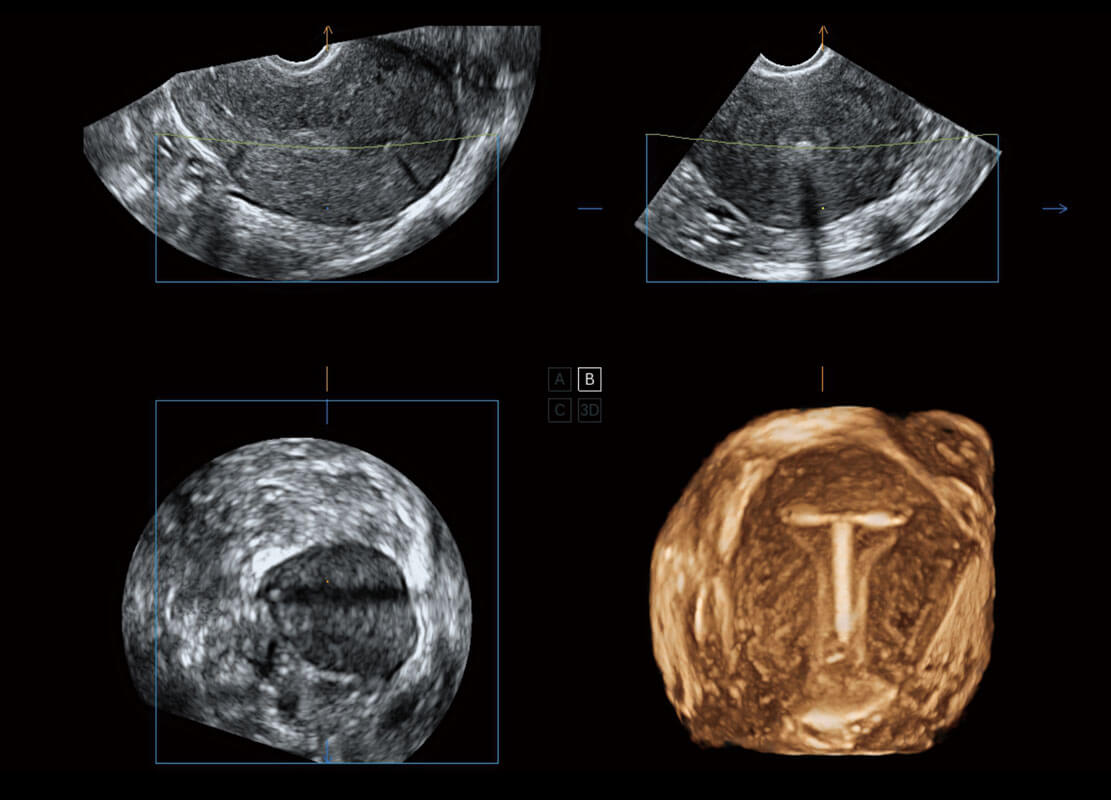

腔內(nèi)三維-宮內(nèi)節(jié)育器

P60為盆底超聲檢查提供應(yīng)用方案,多種腔內(nèi)及腹部容積探頭提供從二維、三維到四維的優(yōu)異圖像品質(zhì),實時快速三維容積數(shù)據(jù)獲取,專業(yè)的測量工具包等人性化設(shè)計,為超聲醫(yī)生診斷提供有力保障。